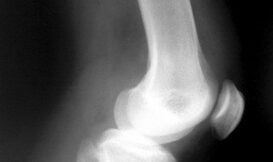

如果你是 3千多萬的美國人其中一員的話,那麼你就會處在骨質疏鬆症的風險*底下,你得知道該如何強化與保護你的骨骼是很重要的一件事情。骨質疏鬆症的意思就是骨頭的孔洞變多與脆弱,稍微遇到外力就可能導致骨折。